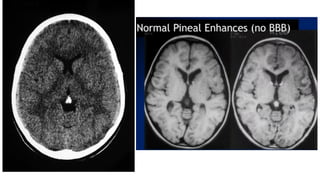

• It does not have a blood brain barrier like any other gland for easy diffusion of

the hormones into the blood streams

CT Findings

• Pineal cysts appear as well circumscribed fluid density lesions.

• A thin rim calcification is seen in ~25%.

• Thin, smooth peripheral enhancement is also often seen.

• The internal cerebral veins are elevated and splayed by the cyst.

• #42 CT of the brain demonstrates no focal mass or abnormality. Incidental note is made of a 20 mm pineal cyst.

• #43 Incidentally well-circumscribed fluid density lesion with rim calcification is seen at pineal topography with no contrast enhancement.